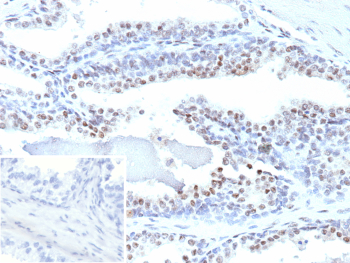

Immunohistochemistry analysis of ERG in human prostate carcinoma tissue. Formalin-fixed, paraffin-embedded human prostate carcinoma tissue was stained using ERG/Prostate cancer ERG antibody (clone ERG1/12589), showing distinct nuclear staining in tumor epithelial cells consistent with prostate cancer-associated ERG expression. Heat-induced epitope retrieval was performed by heating tissue sections in 10 mM Tris with 1 mM EDTA, pH 9.0, at 95oC for 45 minutes, followed by cooling at room temperature for 20 minutes. Inset shows PBS substituted for the primary antibody as a secondary-only negative control.